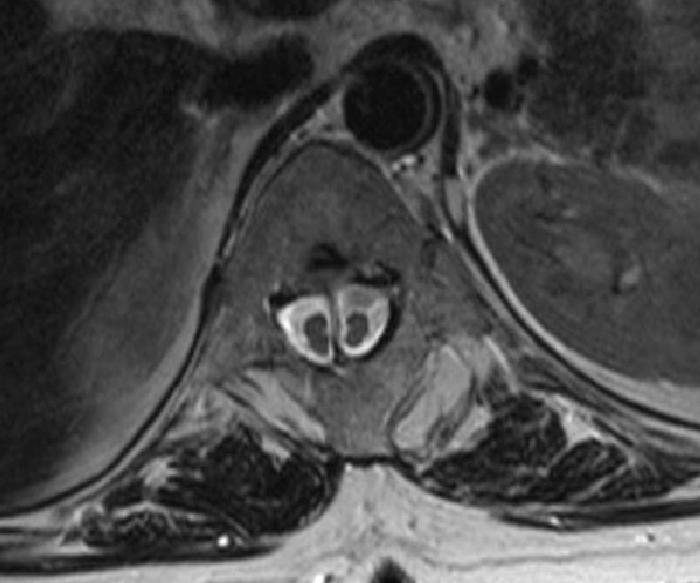

Bifid kord, ayrık omurilik sendromu da denen bu tablo, yani diastematomyeli yarık omurilik anlamına gelir. Genellikle omurga kemiğinin …

Bifid kord, ayrık omurilik sendromu da denen bu tablo, yani diastematomyeli yarık omurilik anlamına gelir. Genellikle omurga kemiğinin ortasındaki kanal içinde uzanan tek bir organ iken, bir kemik yapı veya sert bir zar tarafından omurilik ikiye bölünmüş durumdadır. Bu anomalinin üstü normal bir cilt ile örtülü olduğu için dışarıdan görülmez; ancak çok detaylı radyolojik incelemeler sonucunda ortaya çıkar. Bir çocuğun veya bebeğin sinir sistemi muayenesi sırasında ortaya çıkan bir takım bulgular böyle bir durumdan şüphelenilmesini sağlayabilmekte ise de, bu anomali genellikle daha ileri yaşlarda bir takım ağır egzersizler sırasında veya doğum sırasında ortaya çıkabilen ani felçlerle anlaşılır. Böyle bir durum tespit edildiğinde hastanın deneyimli bir beyin cerrahı tarafından bir an önce ameliyat edilmesi gerekir. Tabii ki günümüzde bu işlem omuriliğin işlevleri ameliyat sırasında izlenmekte iken, yani nöromonitörizasyon altında yapılmaktadır.